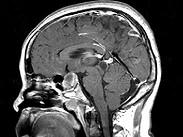

问题 女,45岁,垂体瘤术后7年,2个月前开始诉头痛,视物多模糊,请根据所提供图像,选择最可能的诊断()

选项 A.垂体瘤术后改变 B.垂体瘤术后恶变 C.垂体瘤术后出血 D.(垂体)嫌色细胞腺瘤(复发性) E.颅咽管瘤

答案 D